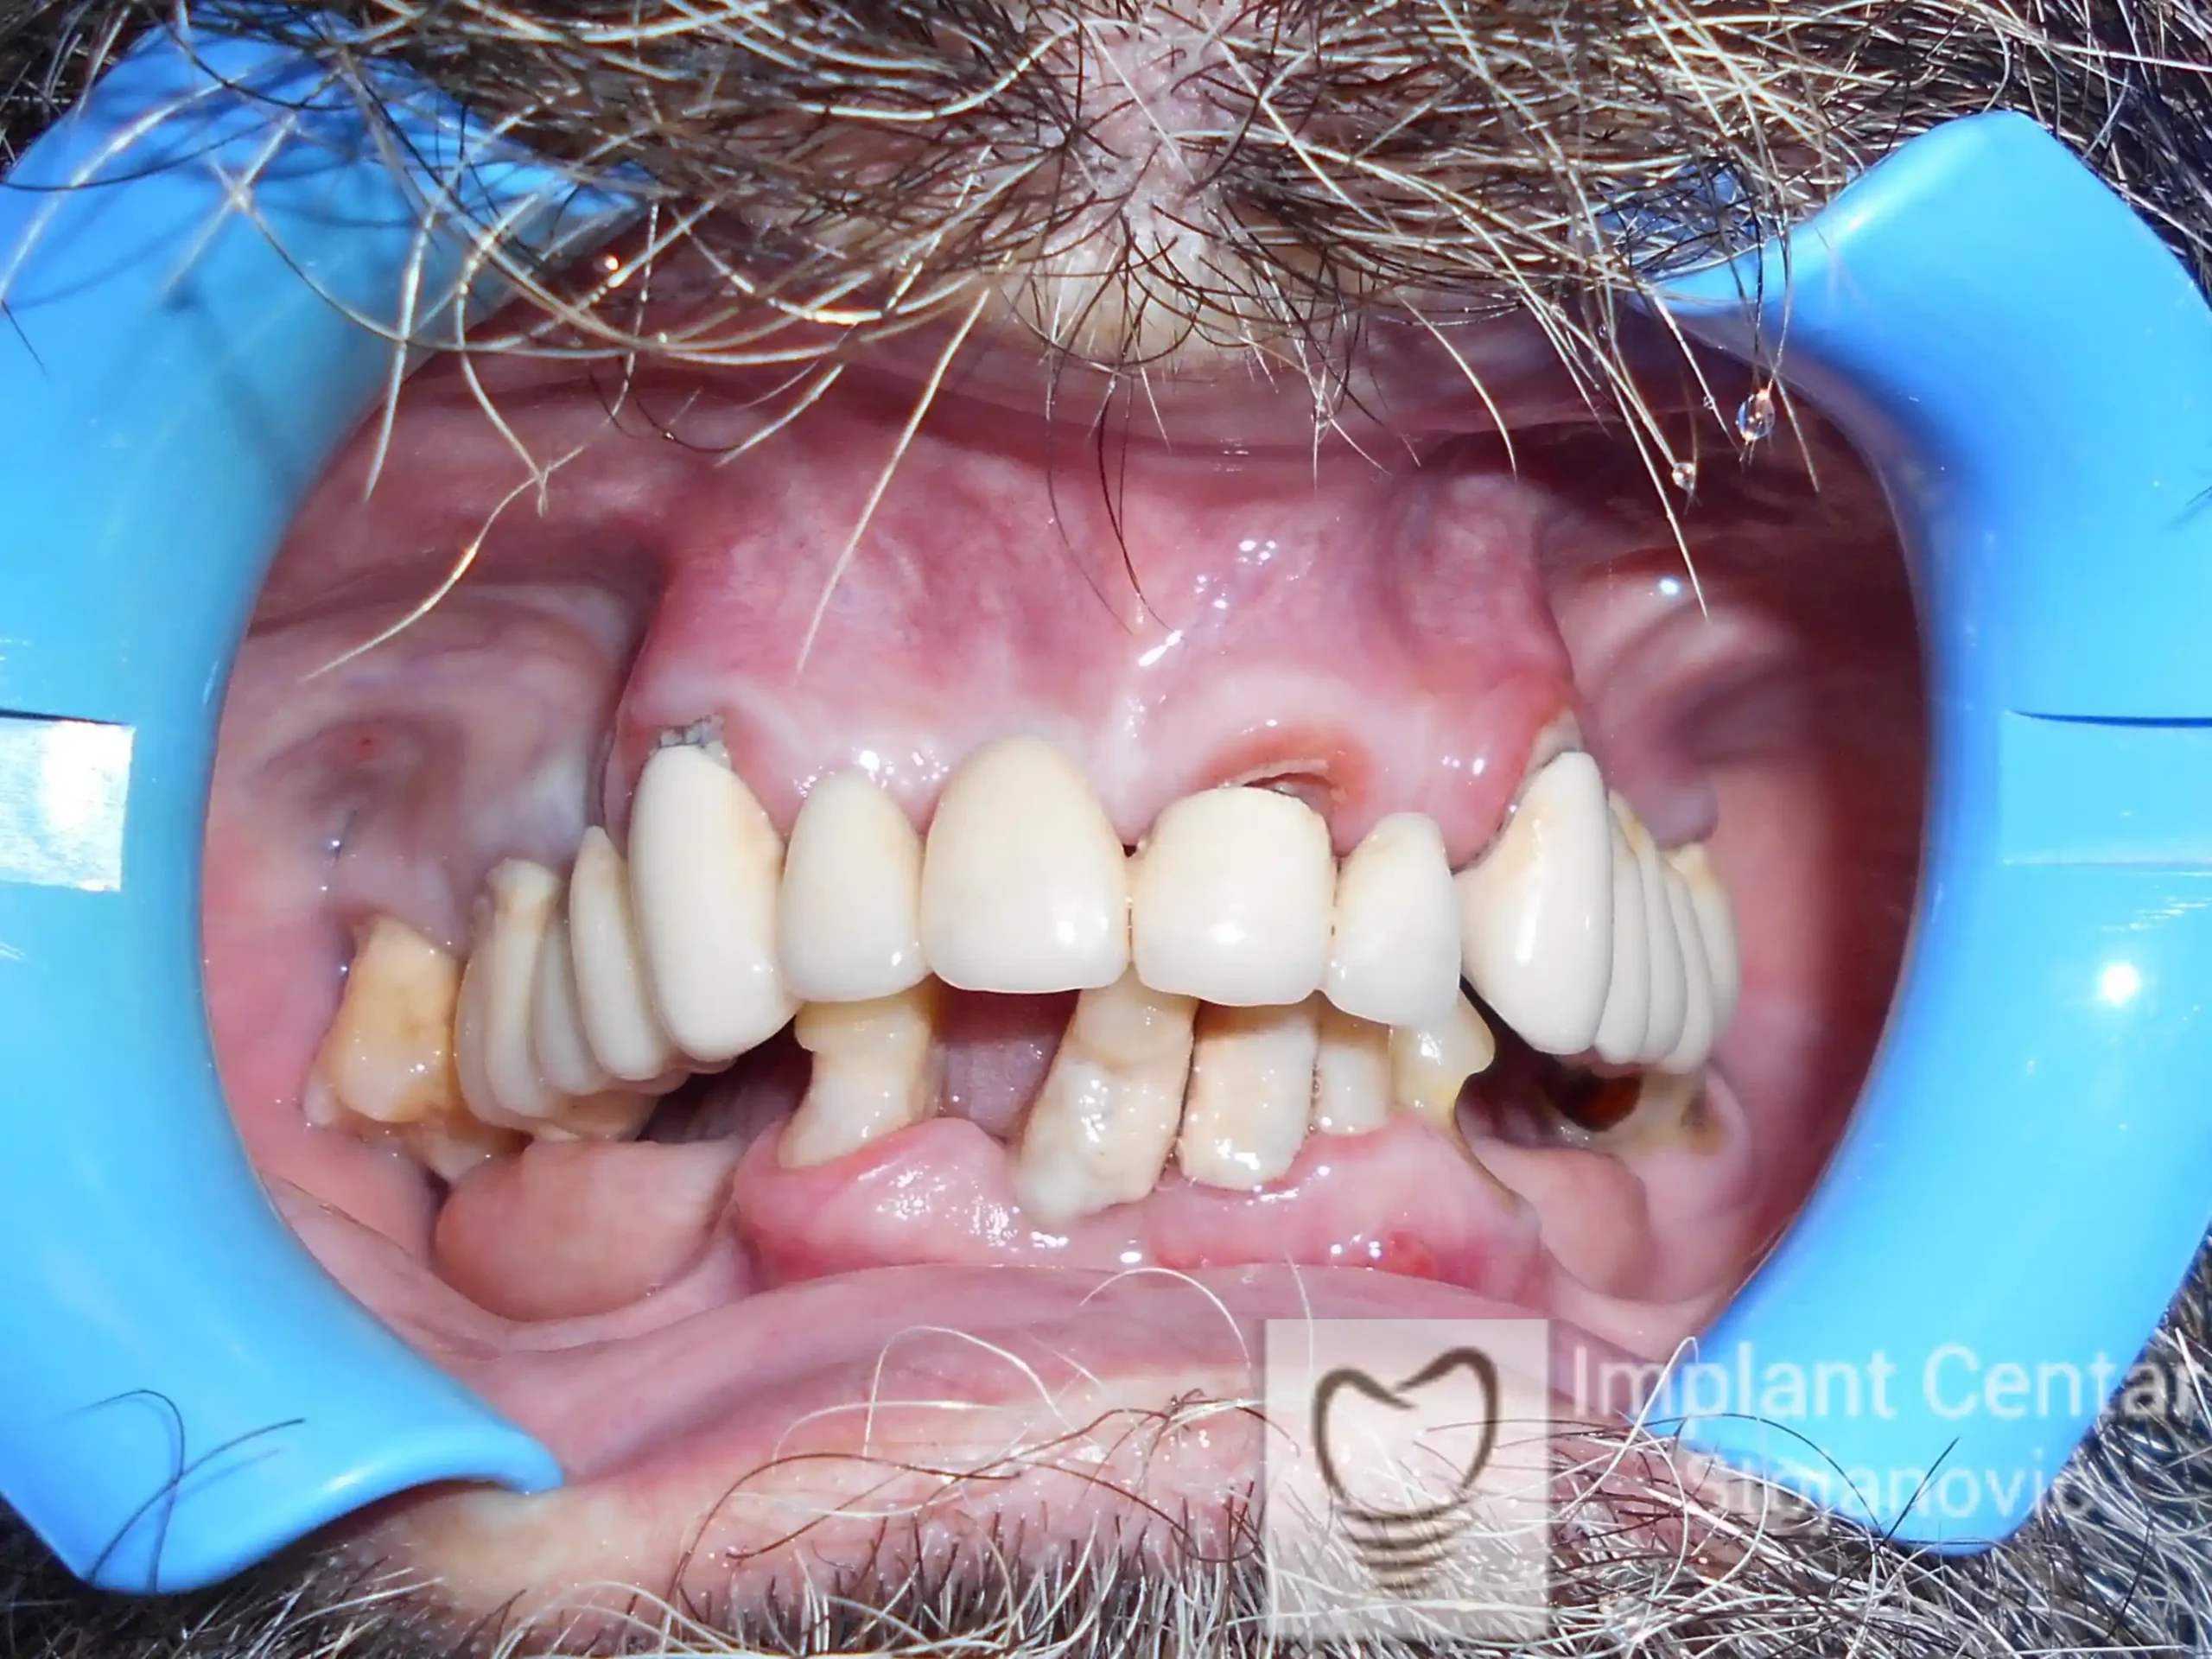

Pacijent sa rascepom usne, nepca i alveolarnog grebena uspešno je rehabilitovan fiksnim protetskim radom na implantatima. Pre dolaska u našu ordinaciju, pacijent je u gornjoj vilici nosio totalnu protezu preko preostalih zuba, dok je u donjoj vilici bio zbrinut parcijalnom mobilnom protezom. Tokom višegodišnje potrage za adekvatnim rešenjem, pacijent nije uspeo da pronađe zadovoljavajuću terapijsku opciju ni u zemlji ni u inostranstvu.

Nakon detaljnog kliničkog pregleda i analize radioloških snimaka, izrađen je sveobuhvatan plan terapije sa ciljem uklanjanja mobilnih proteza i postizanja maksimalne funkcionalne i estetske rehabilitacije. Zbog loše biološke vrednosti preostalih zuba, doneta je odluka o njihovom vađenju i ugradnji dentalnih implantata.

Poseban terapijski izazov predstavljalo je premošćavanje defekta nastalog usled rascepa, kao i ograničena količina raspoložive kosti u gornjoj vilici. Primenom većeg broja implantata i odgovarajućih procedura nadoknade kosti, postignuta je stabilna osnova za fiksni protetski rad.

Tokom perioda oseointegracije, pacijent je bio zbrinut fiksnim privremenim krunicama, čime je već pet dana nakon intervencije obezbeđena potpuna funkcionalna i estetska rehabilitacija. Nakon završetka perioda integracije implantata, izrađeni su definitivni cirkonijum-keramički mostovi na implantatima.